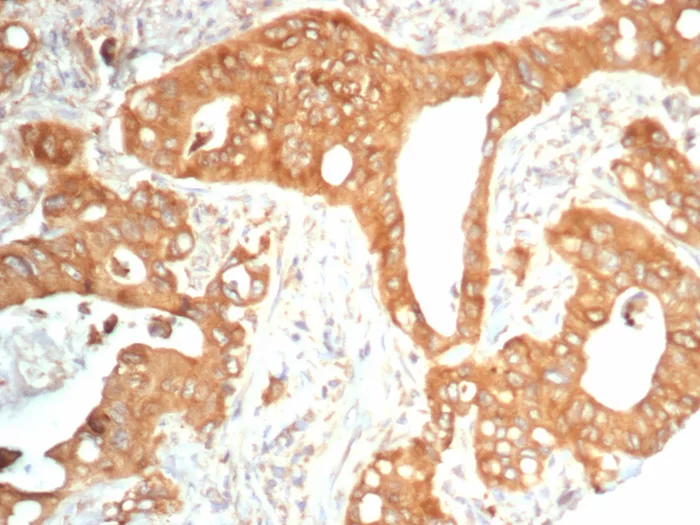

Formalin-fixed, paraffin-embedded human colon carcinoma stained with NTRK2 / TRKb Mouse Monoclonal Antibody (NTRK2/4673). HIER: Tris/EDTA, pH9.0, 45min. 2°C: HRP-polymer, 30min. DAB, 5min.